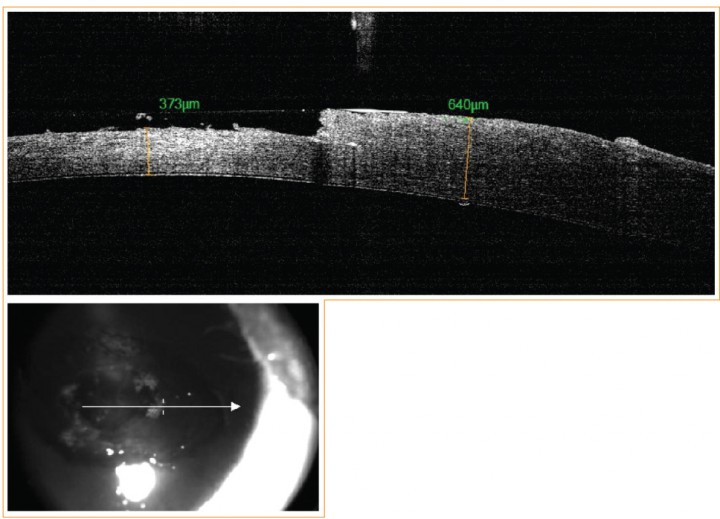

Cuatro semanas más tarde se realizó queratectomía superficial del OD bajo anestesia general. La segunda OCT, intraquirúrgica, mostró tras queratectomía un espesor corneal de 360 µm de media en el centro de la lesión y un espesor corneal perilesional de 680 µm (Fig. 2). Se optó por realizar un injerto multicapa de membrana pericárdica porcina congelada. El injerto se suturó con Nylon 9/0, y se recubrió con tarsorrafia de membrana nictitante (MN) con Nylon de 4/0 suturada al fórnix conjuntival superior. La medicación postquirúrgica instaurada fue la misma que se recetó previamente y se añadió marbofloxacino (Marbocyl®, Vétoquinol Especialidades Farmacéuticas S.A., Madrid) a 2 mg/kg/24 h por vía oral durante 7 días.

<p>OCT intraquirúrgica del ojo derecho.</p>

Figura 2

OCT intraquirúrgica del ojo derecho.